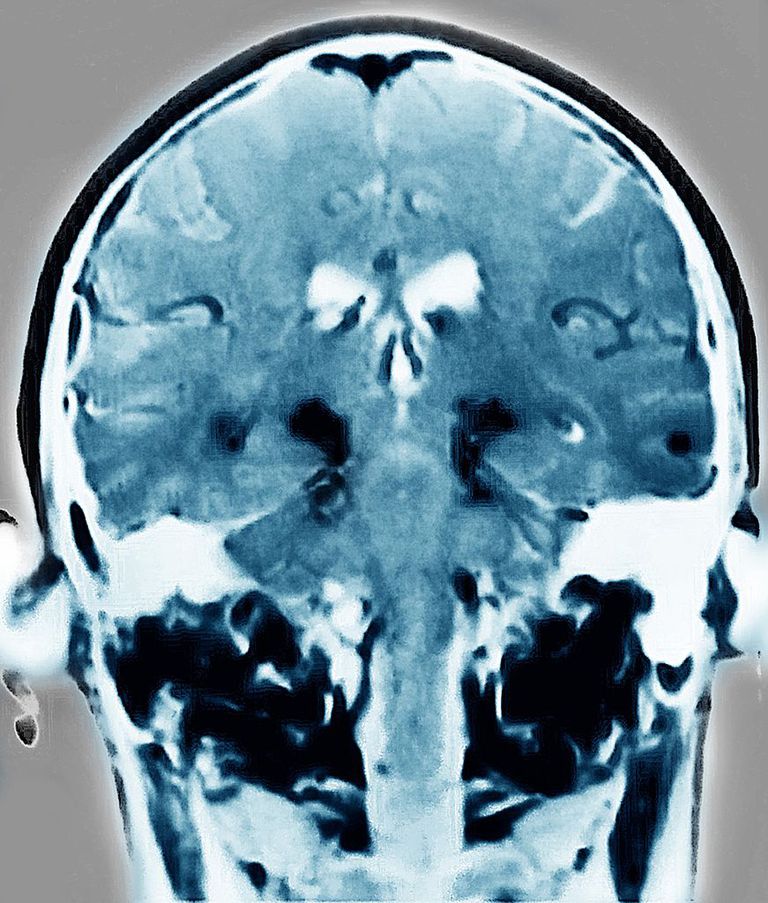

Una nueva prueba de la conexión del sistema cerebo-intestino...